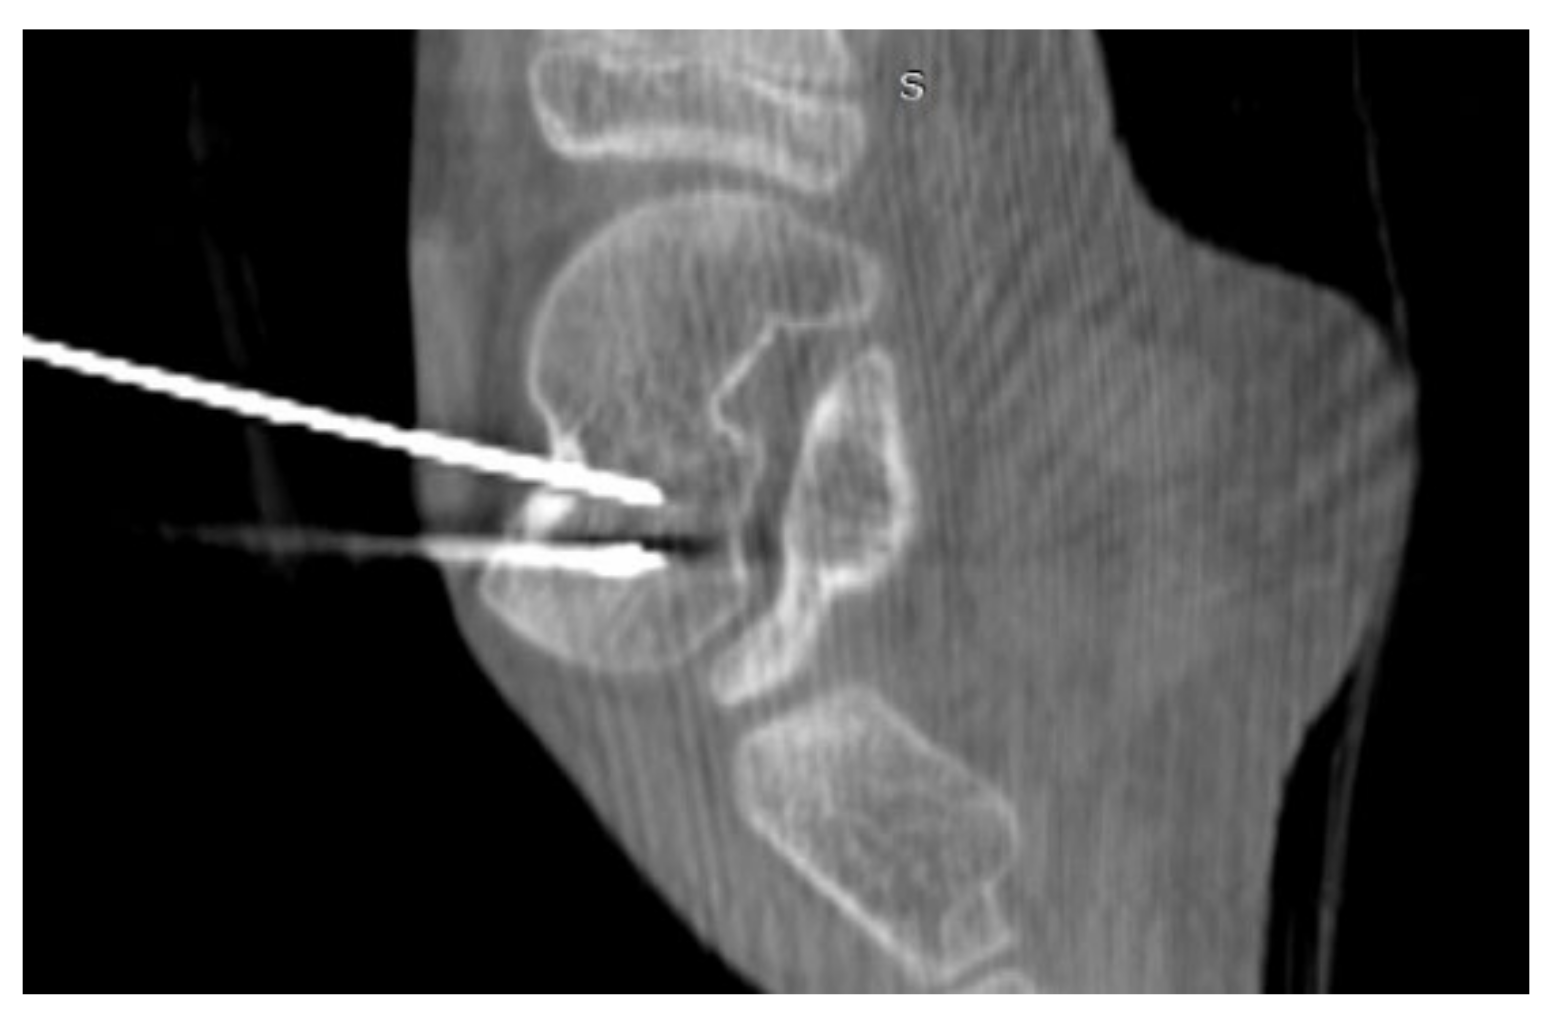

3.4. Case 4: OO Masking as a Fatigue Fracture

A 31-year-old male patient with post-exercise and night pain was seen at an orthopaedic outpatient clinic for diagnosis. The patient underwent a pelvic X-ray and an MRI scan of the right hip joint. The MRI description suggested a suspected fatigue fracture of the right femoral neck (Figure 8). The patient was qualified for surgery. Under general anaesthesia, internal stabilisation was made with three cannulated screws (Figure 9). During the following six months after surgery, the pain did not resolve. During further diagnosis, the patient had a CT scan of the hip joints. The examination revealed a focus of OO of 10 × 9 × 6 mm in the right femoral neck (Figure 10). The patient underwent thermoablation with intraoperative 3D navigation without complications (Figure 11). The VAS score of pain on the day of surgery was 7. Night and postoperative pain resolved completely. The VAS score on examination 3 months after surgery was 0. Cannulated screws were not removed.

Figure 11.

Intraoperative photographs during thermoablation with 3D navigation. Cannulated screws were unscrewed for the time of ablation, and reinserted after the procedure.